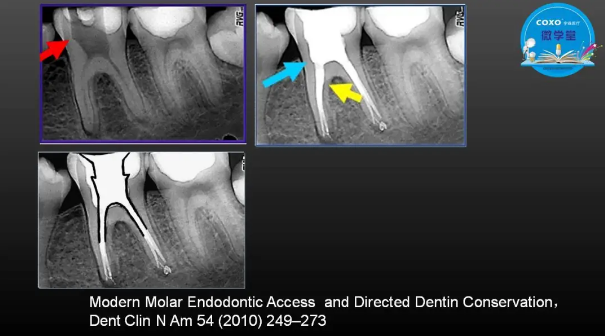

主任醫(yī)師,牙體牙髓副主任, 廣東省口腔醫(yī)院牙體牙髓科 主任醫(yī)師。2003年碩士研究生畢業(yè),研究方向?yàn)檠荔w牙髓病學(xué),擅長(zhǎng)于牙體牙髓病的診斷、齲齒、牙髓炎、根尖周病的治療以及前牙美容修復(fù)。